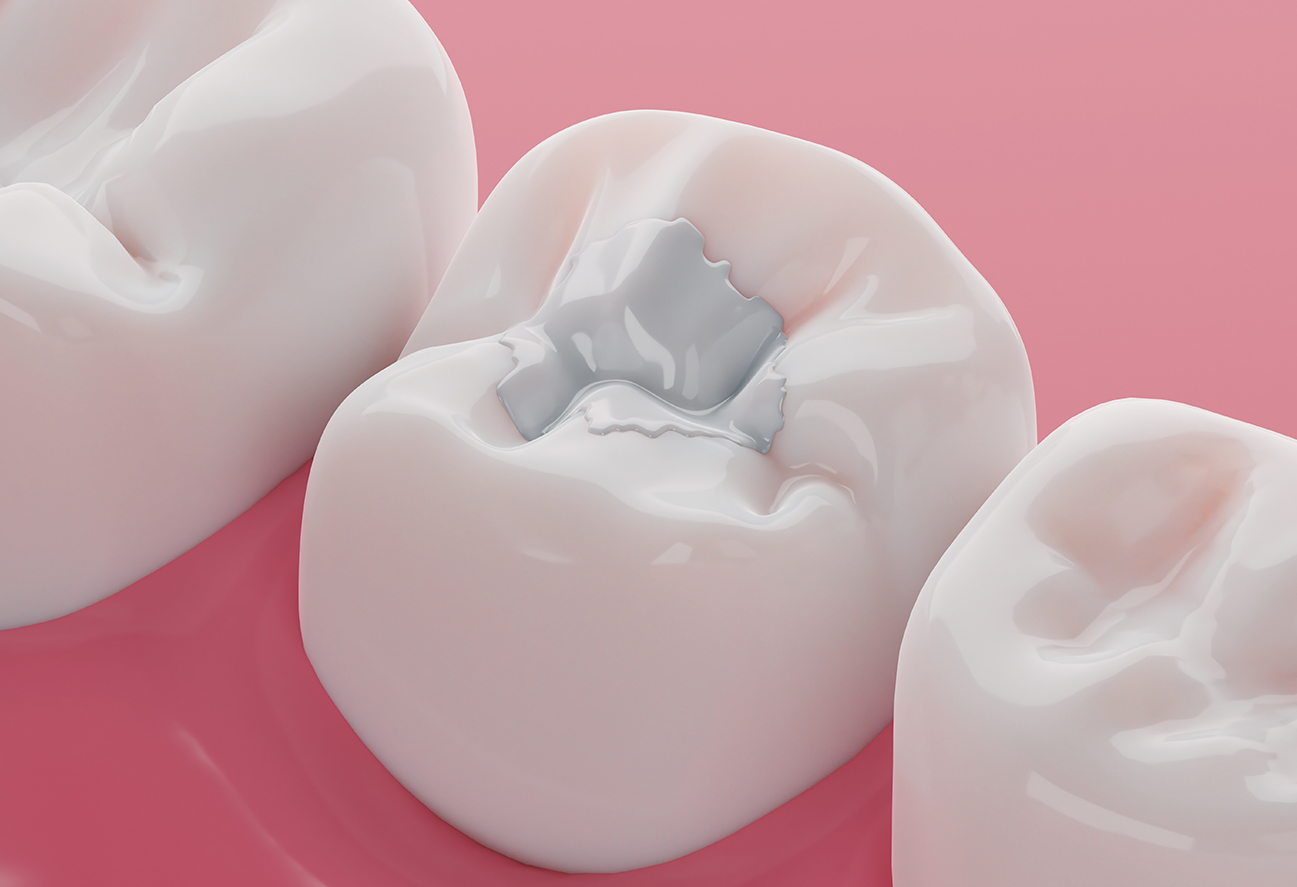

Your comfort is our priority. We typically use local anaesthetic to make the procedure as pain-free as possible. Depending on your needs, we offer both durable amalgam fillings and natural-looking white composite fillings, allowing you to choose the best option for longevity or aesthetics.

Amalgam Fillings

Amalgam fillings are a durable and long-lasting option for restoring teeth affected by decay. Known for their strength, they are ideal for back teeth that endure heavy chewing forces. At Diamond Dental Spa, our experienced dentists use amalgam fillings to provide reliable protection, helping maintain the function and integrity of your teeth over many years. We are best in town to offers amalgam fillings in woodland hills. Book Your appooinment today.